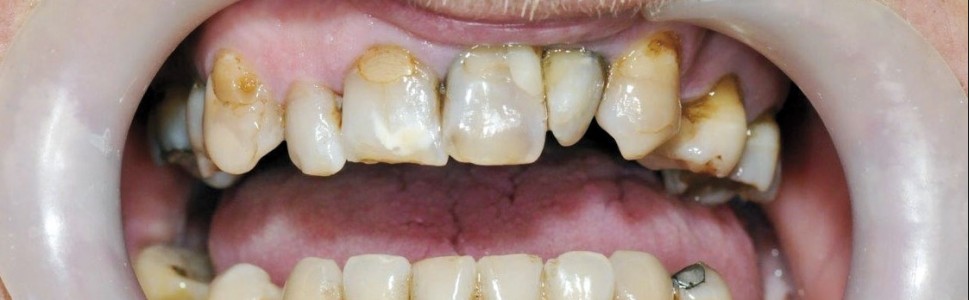

Pacjent B.J., lat 45, zgłosił się do gabinetu w celu poprawy estetyki i uzupełnienia braków zębowych. W badaniu zewnątrzustnym zaobserwowano wysunięcie bródki, wygładzenie bruzdy bródkowo wargowej, pacjent miał charakterystyczne wzmożone napięcie warg i kłopoty z wymową niektórych głosek. W badaniu wewnątrzustnym stwierdzono odwrotne zachodzenie zębów siecznych, zęby ustawione w III klasie Angle’a. Wynik dodatni testu czynnościowego bez poprawy rysów twarzy pozwolił postawić rozpoznanie: przodozgryz całkowity (ryc. 1, 2, 3).

Ponadto w badaniu klinicznym i radiologicznym stwierdzono: konieczność leczenia zachowawczego poszczególnych zębów, obecność braków międzyzębowych w łuku górnym, w łuku dolnym jednostronny brak skrzydłowy i braki międzyzębowe (ryc. 4). Nie stwierdzono zaburzeń w stawie skroniowo żuchwowym. W związku z brakiem pełnych kontaktów zgryzowych wysokość zwarcia była znacznie obniżona.

Pacjent nie zdecydował się na wstępne leczenie ortodontyczne, co przy dodatnim teście czynnościowym według Orlik Grzybowskiej (możliwość ustawienia zębów siecznych tête à tête) przesądziło o próbie protetycznej kompensacji wady zgryzu. Pacjent nie wyraził też zgody na usunięcie zatrzymanego zęba 48. W celu podniesienia zwarcia wykonano tymczasową protezę osiadającą dolną. Zęby górne zaopatrzono w tymczasowe korony i mosty akrylowe. Zaproponowane uzupełnienia miały na celu uzyskanie pełnej akceptacji artykulacyjno zgryzowej układu stomatognatycznego do zaplanowanej wysokości zwarcia. Po 6 miesięcznym okresie adaptacyjnym z zastosowaniem protezy częściowej osiadającej i kontrolnych badaniach radiologicznych i czynnościowych stawu skroniowo żuchwowego oraz braku dolegliwości w wywiadzie, wykonano docelowe uzupełnienia stałe w łuku górnym i dolnym. Docelowy plan leczenia – to uzupełnienia stałe w łuku górnym – korony i mosty na podbudowie metalowej licowane porcelaną, w łuku dolnym – most po stronie prawej. Po stronie lewej przewidziano leczenie implantologiczne.